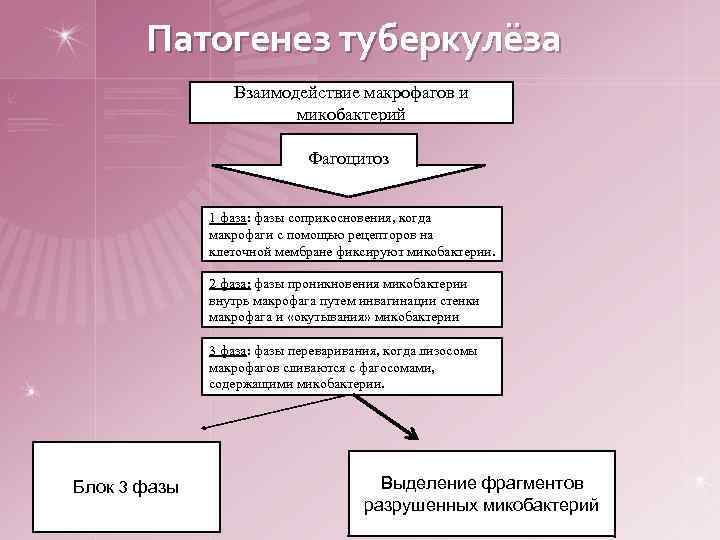

Патогенез туберкулёза Взаимодействие макрофагов и микобактерий Фагоцитоз 1 фаза: фазы соприкосновения, когда макрофаги с помощью рецепторов на клеточной мембране фиксируют микобактерии. 2 фаза: фазы проникновения микобактерии внутрь макрофага путем инвагинации стенки макрофага и «окутывания» микобактерии 3 фаза: фазы переваривания, когда лизосомы макрофагов сливаются с фагосомами, содержащими микобактерии. Блок 3 фазы Выделение фрагментов разрушенных микобактерий